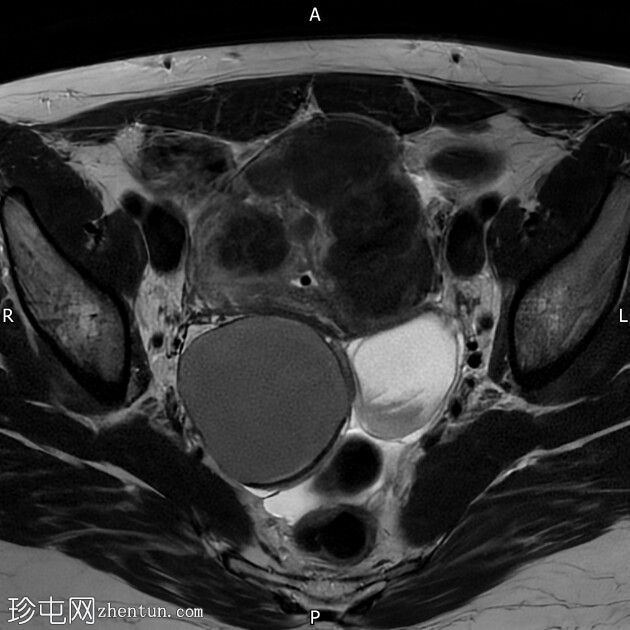

轴位T1加权像

脂肪抑制像

右侧卵巢囊肿,T2加权像呈低信号,T1脂肪抑制像呈高信号,大小为6 x 5.2 cm,符合子宫内膜异位囊肿的影像学表现。

左侧卵巢囊肿,T2加权像呈低信号,T1脂肪抑制像呈高信号,符合子宫内膜异位囊肿的影像学表现。

双侧卵巢粘连于后道格拉斯窝,呈“接吻卵巢征”。

多发性子宫肌瘤。宫内放置宫内节育器。